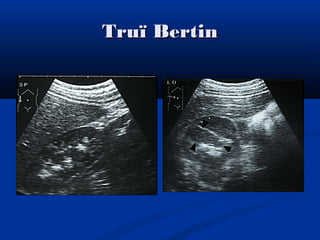

Truï BertinTruï Bertin

Phì ñaïi truï BertinPhì ñaïi truï Bertin

Bieán theå bìnhthöôøngBieán theå bình thöôøng Phì ñaïi truï BertinPhì ñaïi truï Bertin

Phì ñaïi truïBertinPhì ñaïi truï Bertin